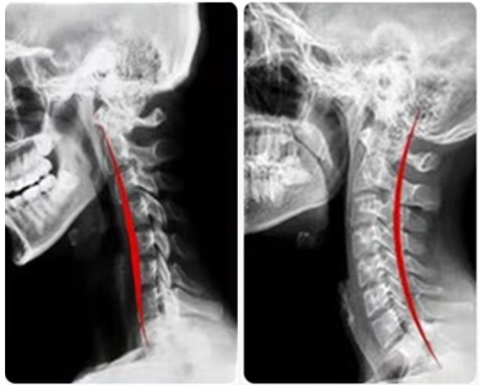

在日常过程中,如果佩戴方法错误,并不能达到“前高后低”的下颌有效支撑(chin support),即:让下颌抬高,使反弓的颈椎恢复轻度前凸的生理弯曲。

只有通过对下颌的支撑和抬举,同时牵引颈椎的长度,才有可能纠正颈椎的前屈后凸畸形,恢复颈椎的生理曲度。